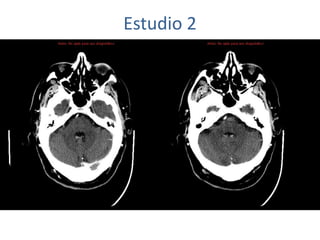

Estudio 2

• Estudio sin y con contraste, con reconstrucciones sagitales y coronales

del estudio con contraste.

Se observa una lesión ocupante de espacio en lóbulo frontal derecho que

presenta un tamaño de 18 x 32 x 22 mm (cc x ap x tr), bilobulada, no del

todo bien delimitada, con realce en anillo irregular, con hipocaptación

central, probablemente por necrosis, y asociada a un extenso edema

vasogénico con efecto masa tanto sobre los surcos de la convexidad

como sobre la cisterna insular, el sistema ventricular y la línea media,

esta última con un desplazamiento de 5 mm a la altura del septo

interventricular.

No se aprecian otras lesiones focales intra o extraaxiales de significación

patológica.

Habría que considerar como primera posibilidad que se tratase de una

lesión metastásica, por bien un tumor primario, aunque no se puede

descartar otras opciones, sin imprescindible correlación con la clínica y

con sus antecedentes.